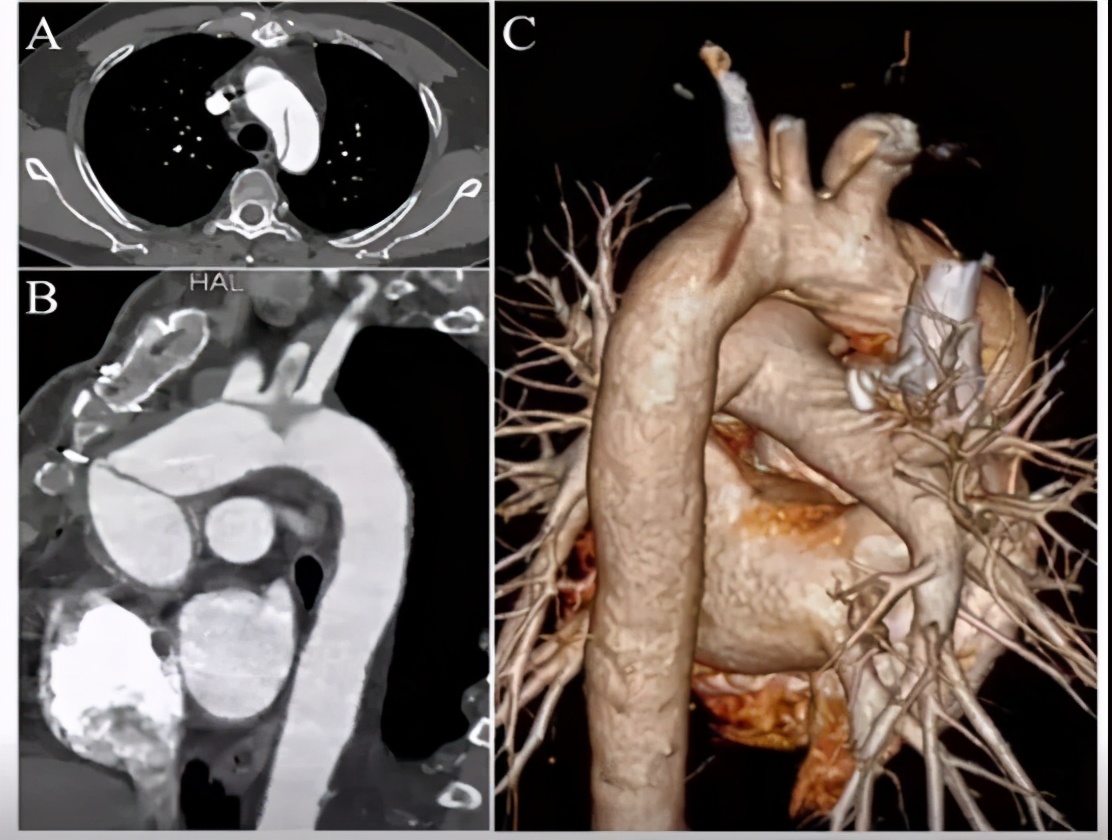

手术策略:弓上三分支原位开窗+主动脉腔内修复术。

手术步骤:股-颈动脉转流;释放远端限制性支架+近端主体支架;无名动脉原位开窗+支架植入;左颈总动脉原位开窗+支架植入;左锁骨下动脉原位开窗+支架植入。

手术要点:注意支架直径的选择与人工血管直径及预计锚定位置的关系;近端锚定区位置判断及预估裸支架位置与人工血管皱褶、冠脉开口的关系;术中超硬导丝的走行,支架输送鞘tip头长度、右冠吻合口及人工瓣膜的保护。